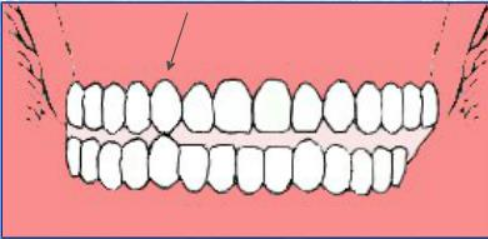

调𬌗的具体方法,只需四步!(附检查方法)